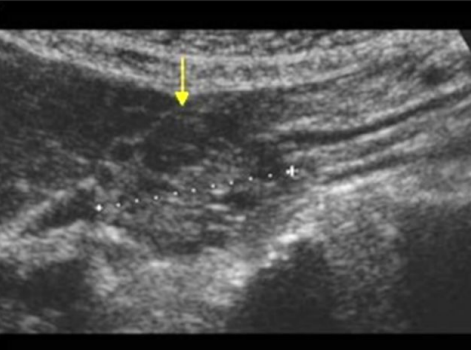

Describe this image

Diagnosis?

Transverse view of the pancreas

Pancreas appears to be swollen/enlarged with increased echogenicity and has peripancreatic fluid

Dx: acute pancreatitis